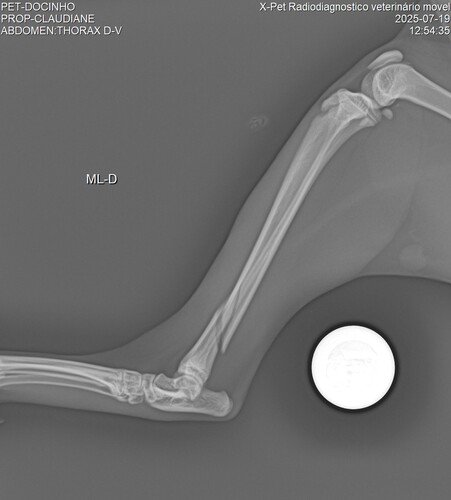

Não podíamos deixa-la na rua, pois ela não resistiria por muito tempo. Então levamos ao veterinário, onde foi feito um Raio X e constatou-se que ela havia fraturado a Tibia e que o tratamento era apenas por meio de uma cirurgia que custava R$ 2.520,00.